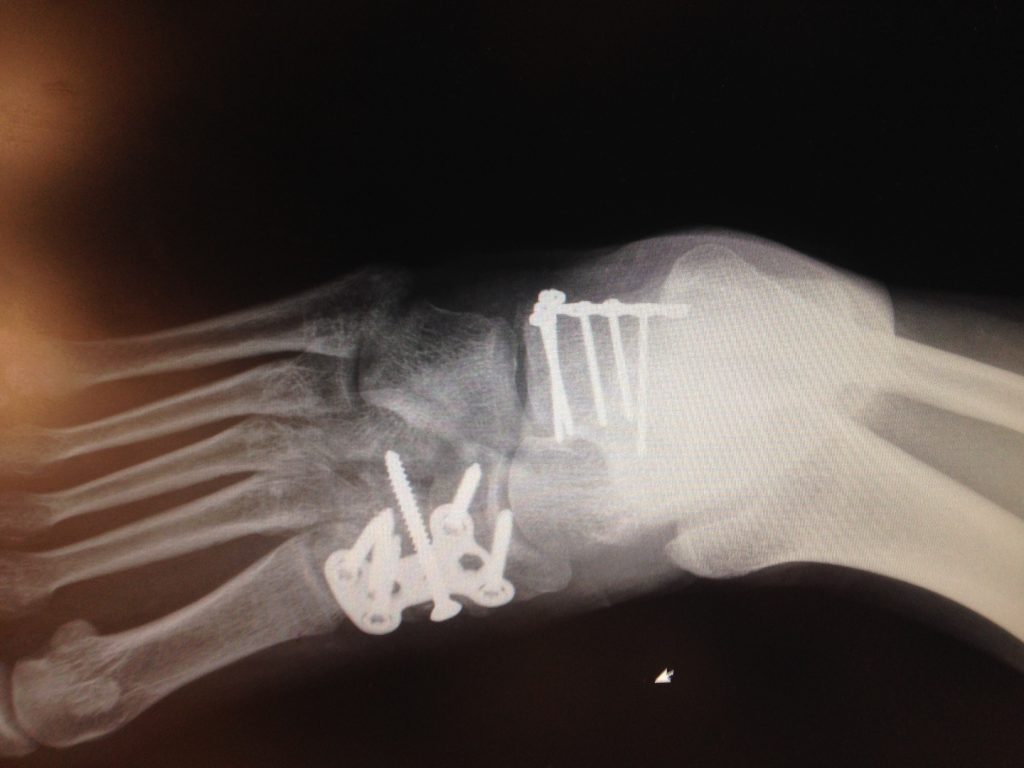

While the accident itself was only a matter of seconds, its impact has been long lasting and completely altered the course of my senior year of high school. They said the entire mid-section of my foot had been crushed, while also fracturing my heel and having to fuse four bones together.

After a five-hour surgery, two plates, six screws and five pins later, my foot was put back together. Now, looking back, a whole six years later, I have run two half marathons and just completed my first New York City Marathon this past November, crushing my individual time goal and without pain. Not a week goes by that I do not think about the wonderful people and doctors at HSS who always kept my spirits up through a year of recovery. I am, and will be, forever grateful to Dr. O'Malley and his team at HSS for giving me the second chance to get Back in the Game.